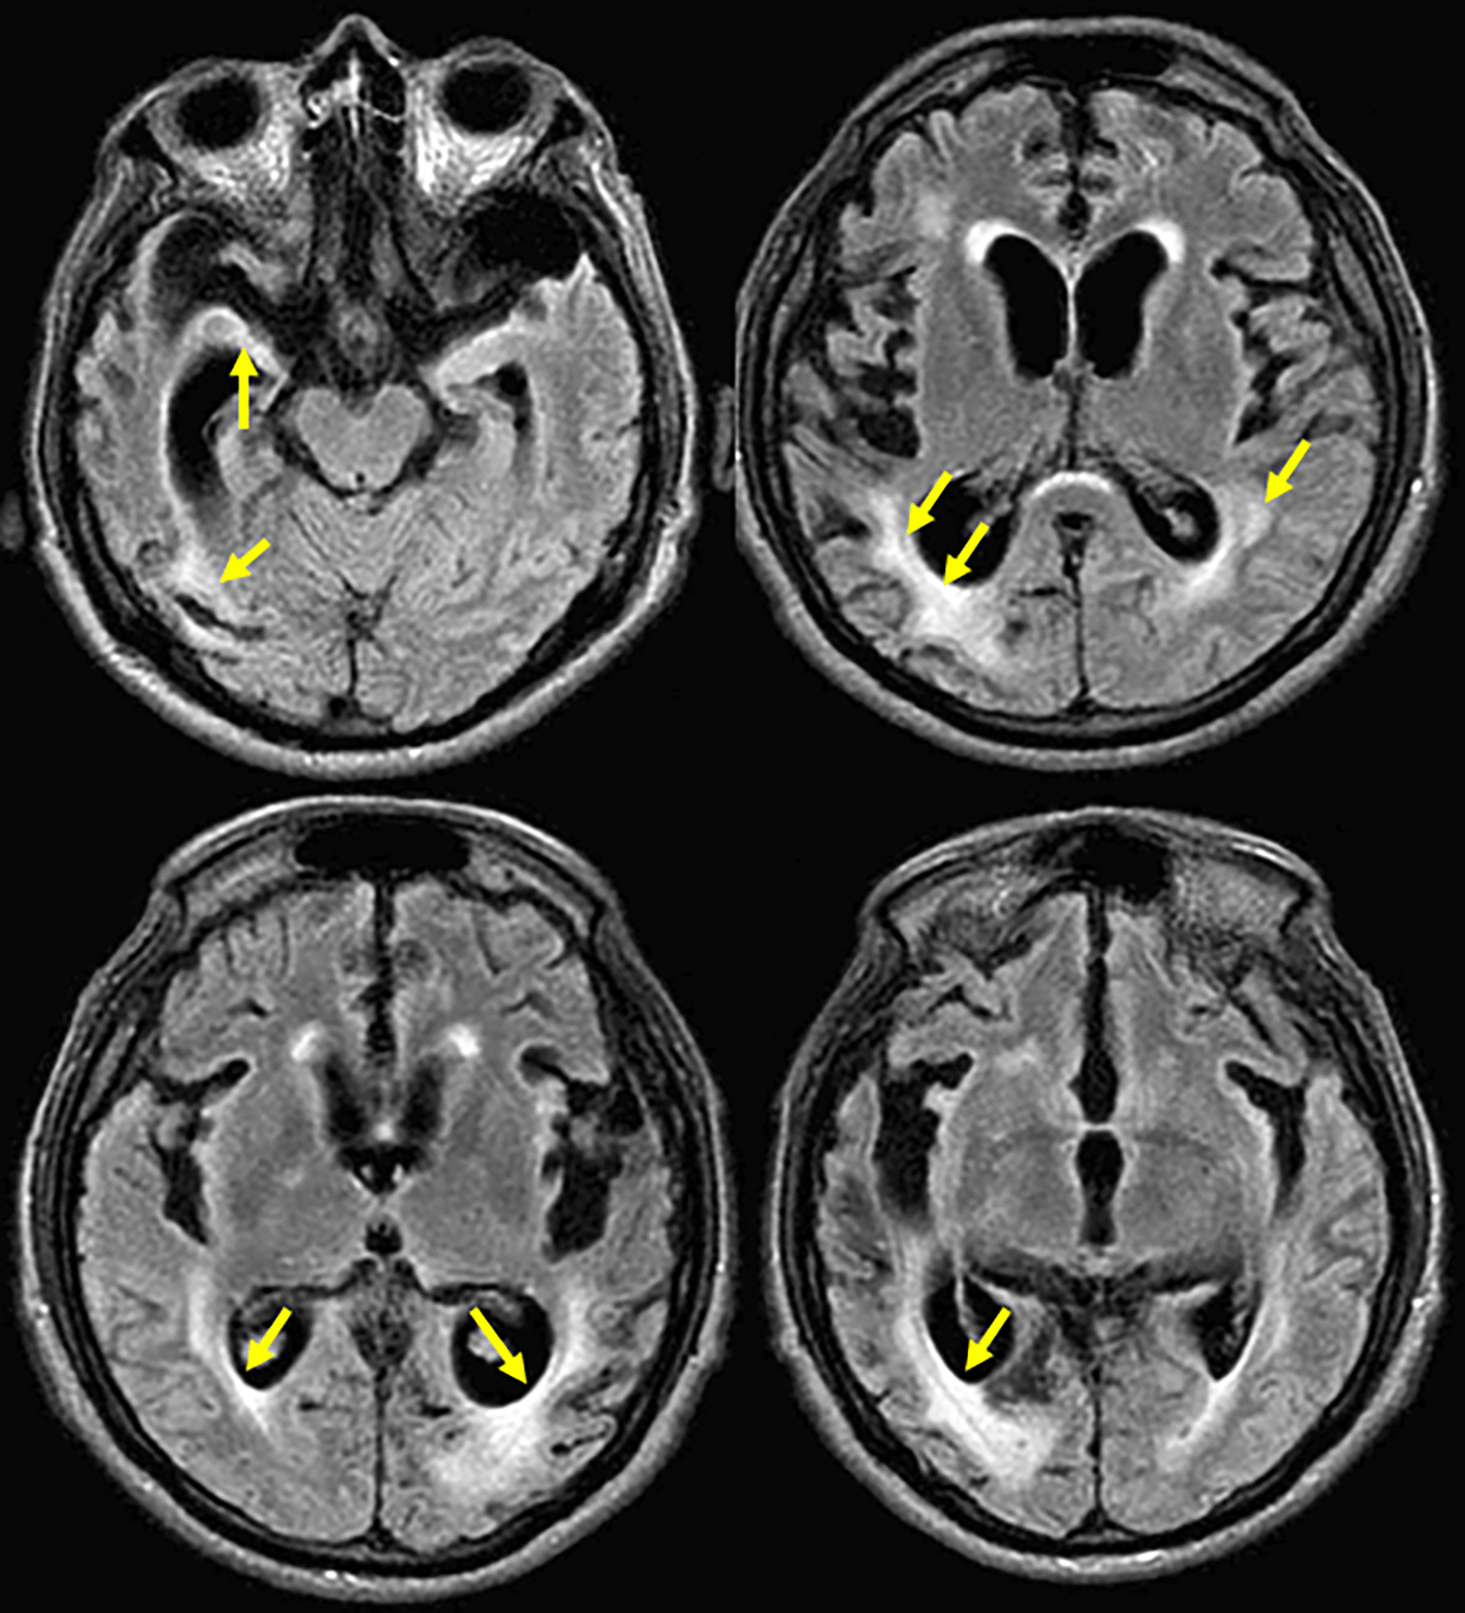

Brain magnetic resonance imaging (MRI) showed moderate to severe cortico-subcortical atrophic changes and subcortical hyperintensities ( Figure 1). Additionally, an EEG was performed, without any alteration. Due to the progressive neurological compromise and the combination neurological findings, patient met the requirement of at least two supportive signs (pyramidal/extrapyramidal and cerebellar/myoclonic features) as defined in the diagnostic criteria for probable CJD. Moreover, the development of early and progressive dementia in the next months, and the MRI suggestive of prion disease, CJD diagnostic was prioritized for exploration. CSF 14-3-3 protein was analyzed by a semi-quantitative Western blot assay in an external reference laboratory. Patient CSF was run alongside negative and positive control samples, and band intensity for 14-3-3 was densitometrically compared to these controls. According to the laboratory’s validated cut-off, the result was classified as strongly positive (‘high titre’), supporting the diagnosis of probable CJD. Symptomatic treatment and palliative care were indicated to the patient.

Axial section in a fluid attenuated inversion recovery (FLAIR) sequence showing hippocampal volume decreased in both temporal lobes with increase of temporal horns predominantly on right side; mild hyperintensity in right caudate nucleus and moderate in periventricular regions with confluent zones in the right parietal region; and moderate to severe atrophic cortical-subcortical with frontotemporal predominance (Hyperintensities highlighted with arrows).

Current reviews indicate that the changes in brain-MRI are bilateral, symmetric, and predominant in basal ganglia and cortical regions,6,26 in addition, 85% show signs of atrophy in the MRI.6 Our case findings are according to this literature, however, in most of the cases with difficult timely diagnosis, the MRI results were inconclusive or normal until the end-stage of the disease, and the most common finding was cortical-subcortical atrophy and basal nuclei hyperintensity.